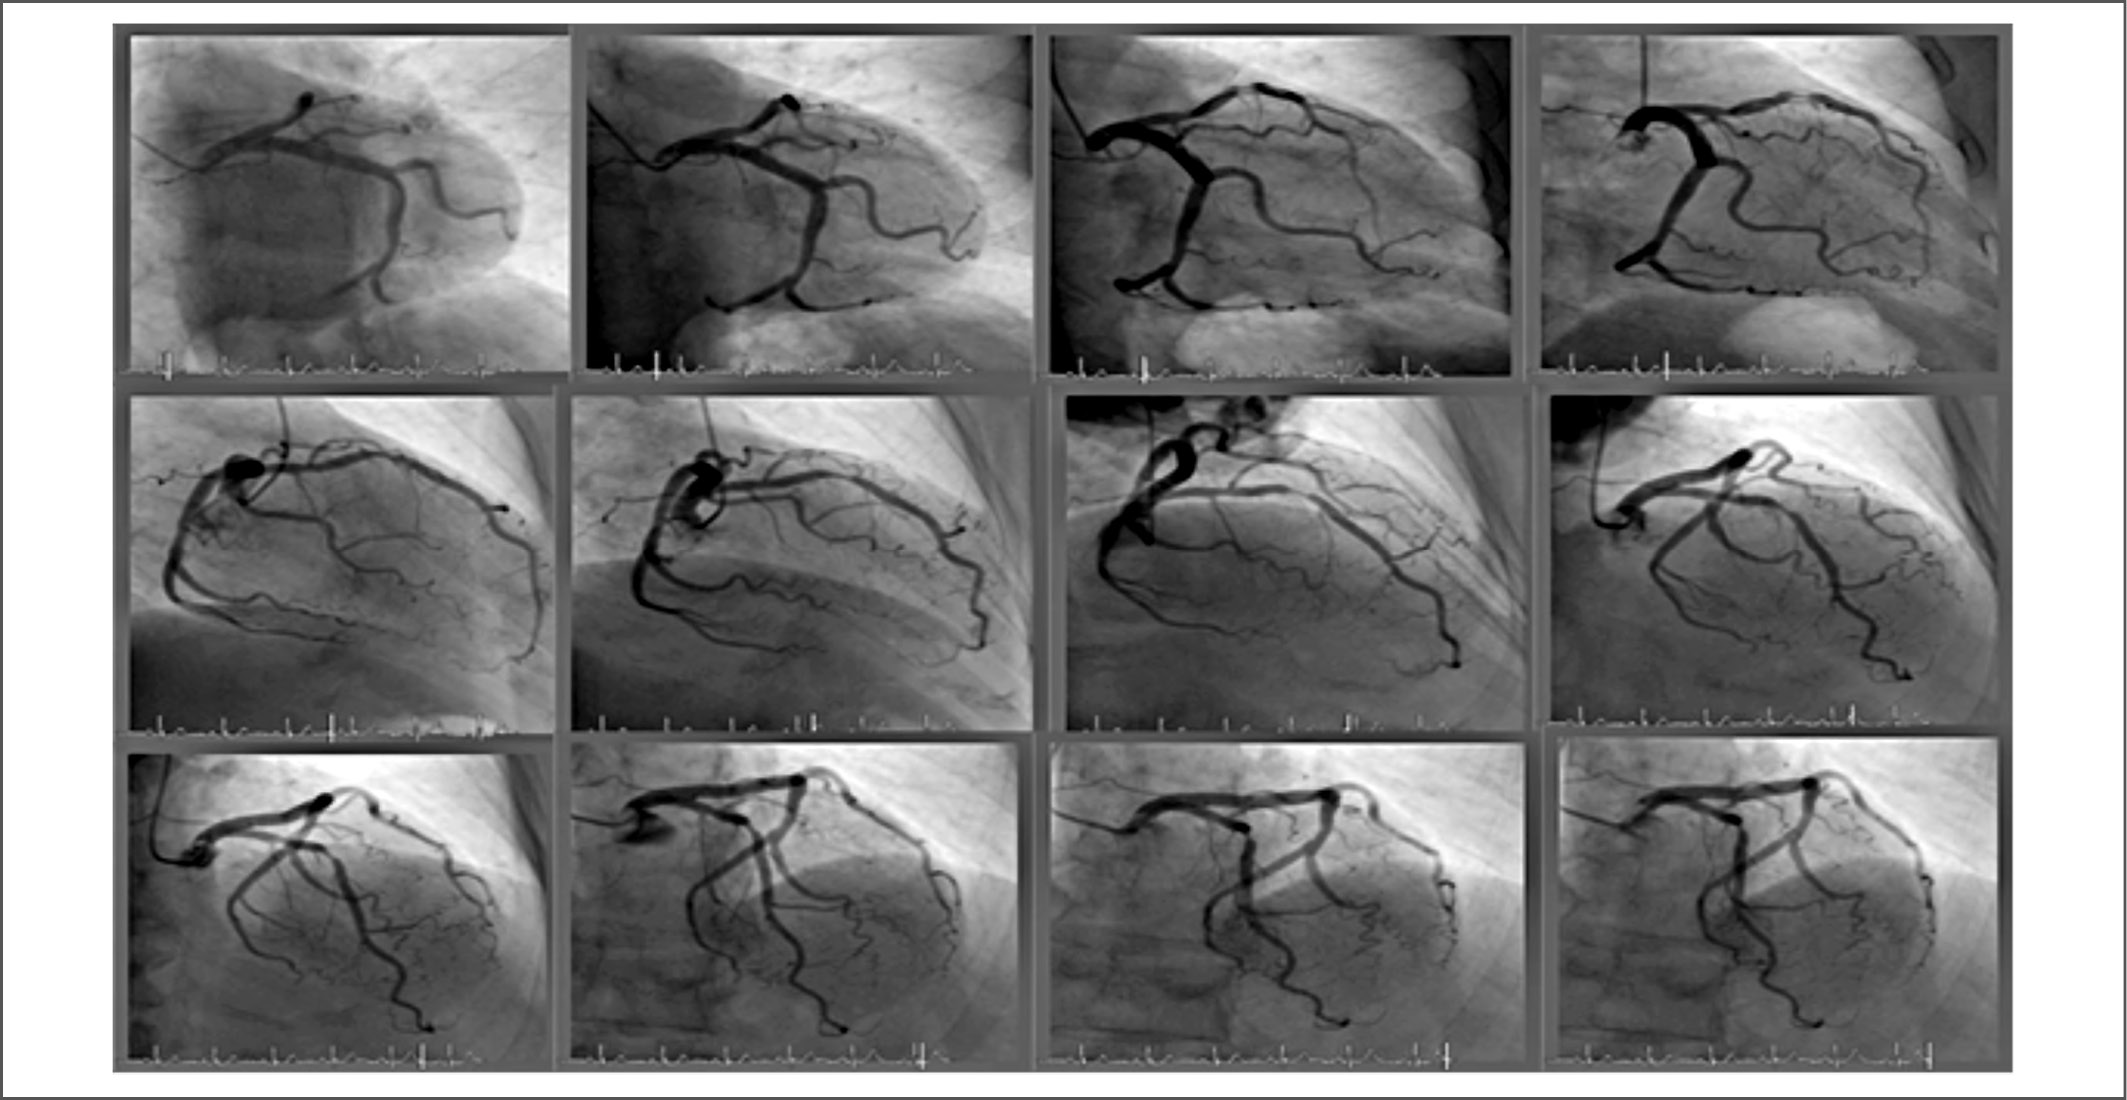

При осмотре установлено снижение АД до 80/50 мм рт. ст. На ЭКГ – картина острого, с подъёмом сегмента ST, инфаркта миокарда (рис. 6). Госпитализирована в отделение реанимации и интенсивной терапии. Больная получала тикагрелор – 180 мг, ацетилсалициловую кислоту – 100 мг, гепарин натрия – 5000 ед внутривенно (однократно). Экстренно выполнена КАГ, на которой стенозирующего атеросклеротического поражения коронарных артерий не выявлено (рис. 7). На ЭКГ от 14.05.2019 г. обнаруженные изменения расценили как инфарктоподобные. Также была выполнена ЭхоКГ (рис. 8).

Рис. 7. На серии КАГ пациентки К. от 14.05.2019 г. все коронарные артерии проходимы, атеросклеротические изменения не определяются.

Fig. 7. On the KAG series of patients K. from 14.05.2019. all coronary arteries are passable, atherosclerotic changes are not defined.